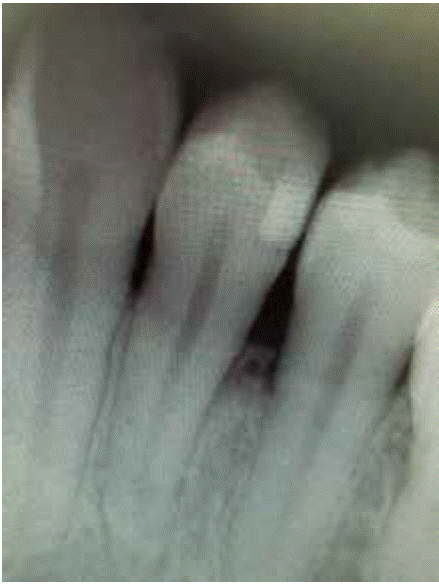

Clinical examination revealed an inflammatory gingival lesion at the level of teeth 3.4 and 3.5. Measuring approximately 15x9 mm. The lesion covered the vestibular side of the clinical crown, it was firm, lobulated, of rugged texture and bleeding upon stimulus (Figures 1and2). Periodontal assessment did not reveal periodontal pockets; presence of plaque was observed, and an O'Leary oral hygiene index of 18.75 was determined. Radiographic evaluation revealed absence of interproximal contact between teeth 3.4 and 3.5 as well as restorative material in the interproximal area (Figure 3).

Figure 3 Periapical X-ray of the lesion area. Absence of interproximal contact between teeth 3.4 and 3.5.